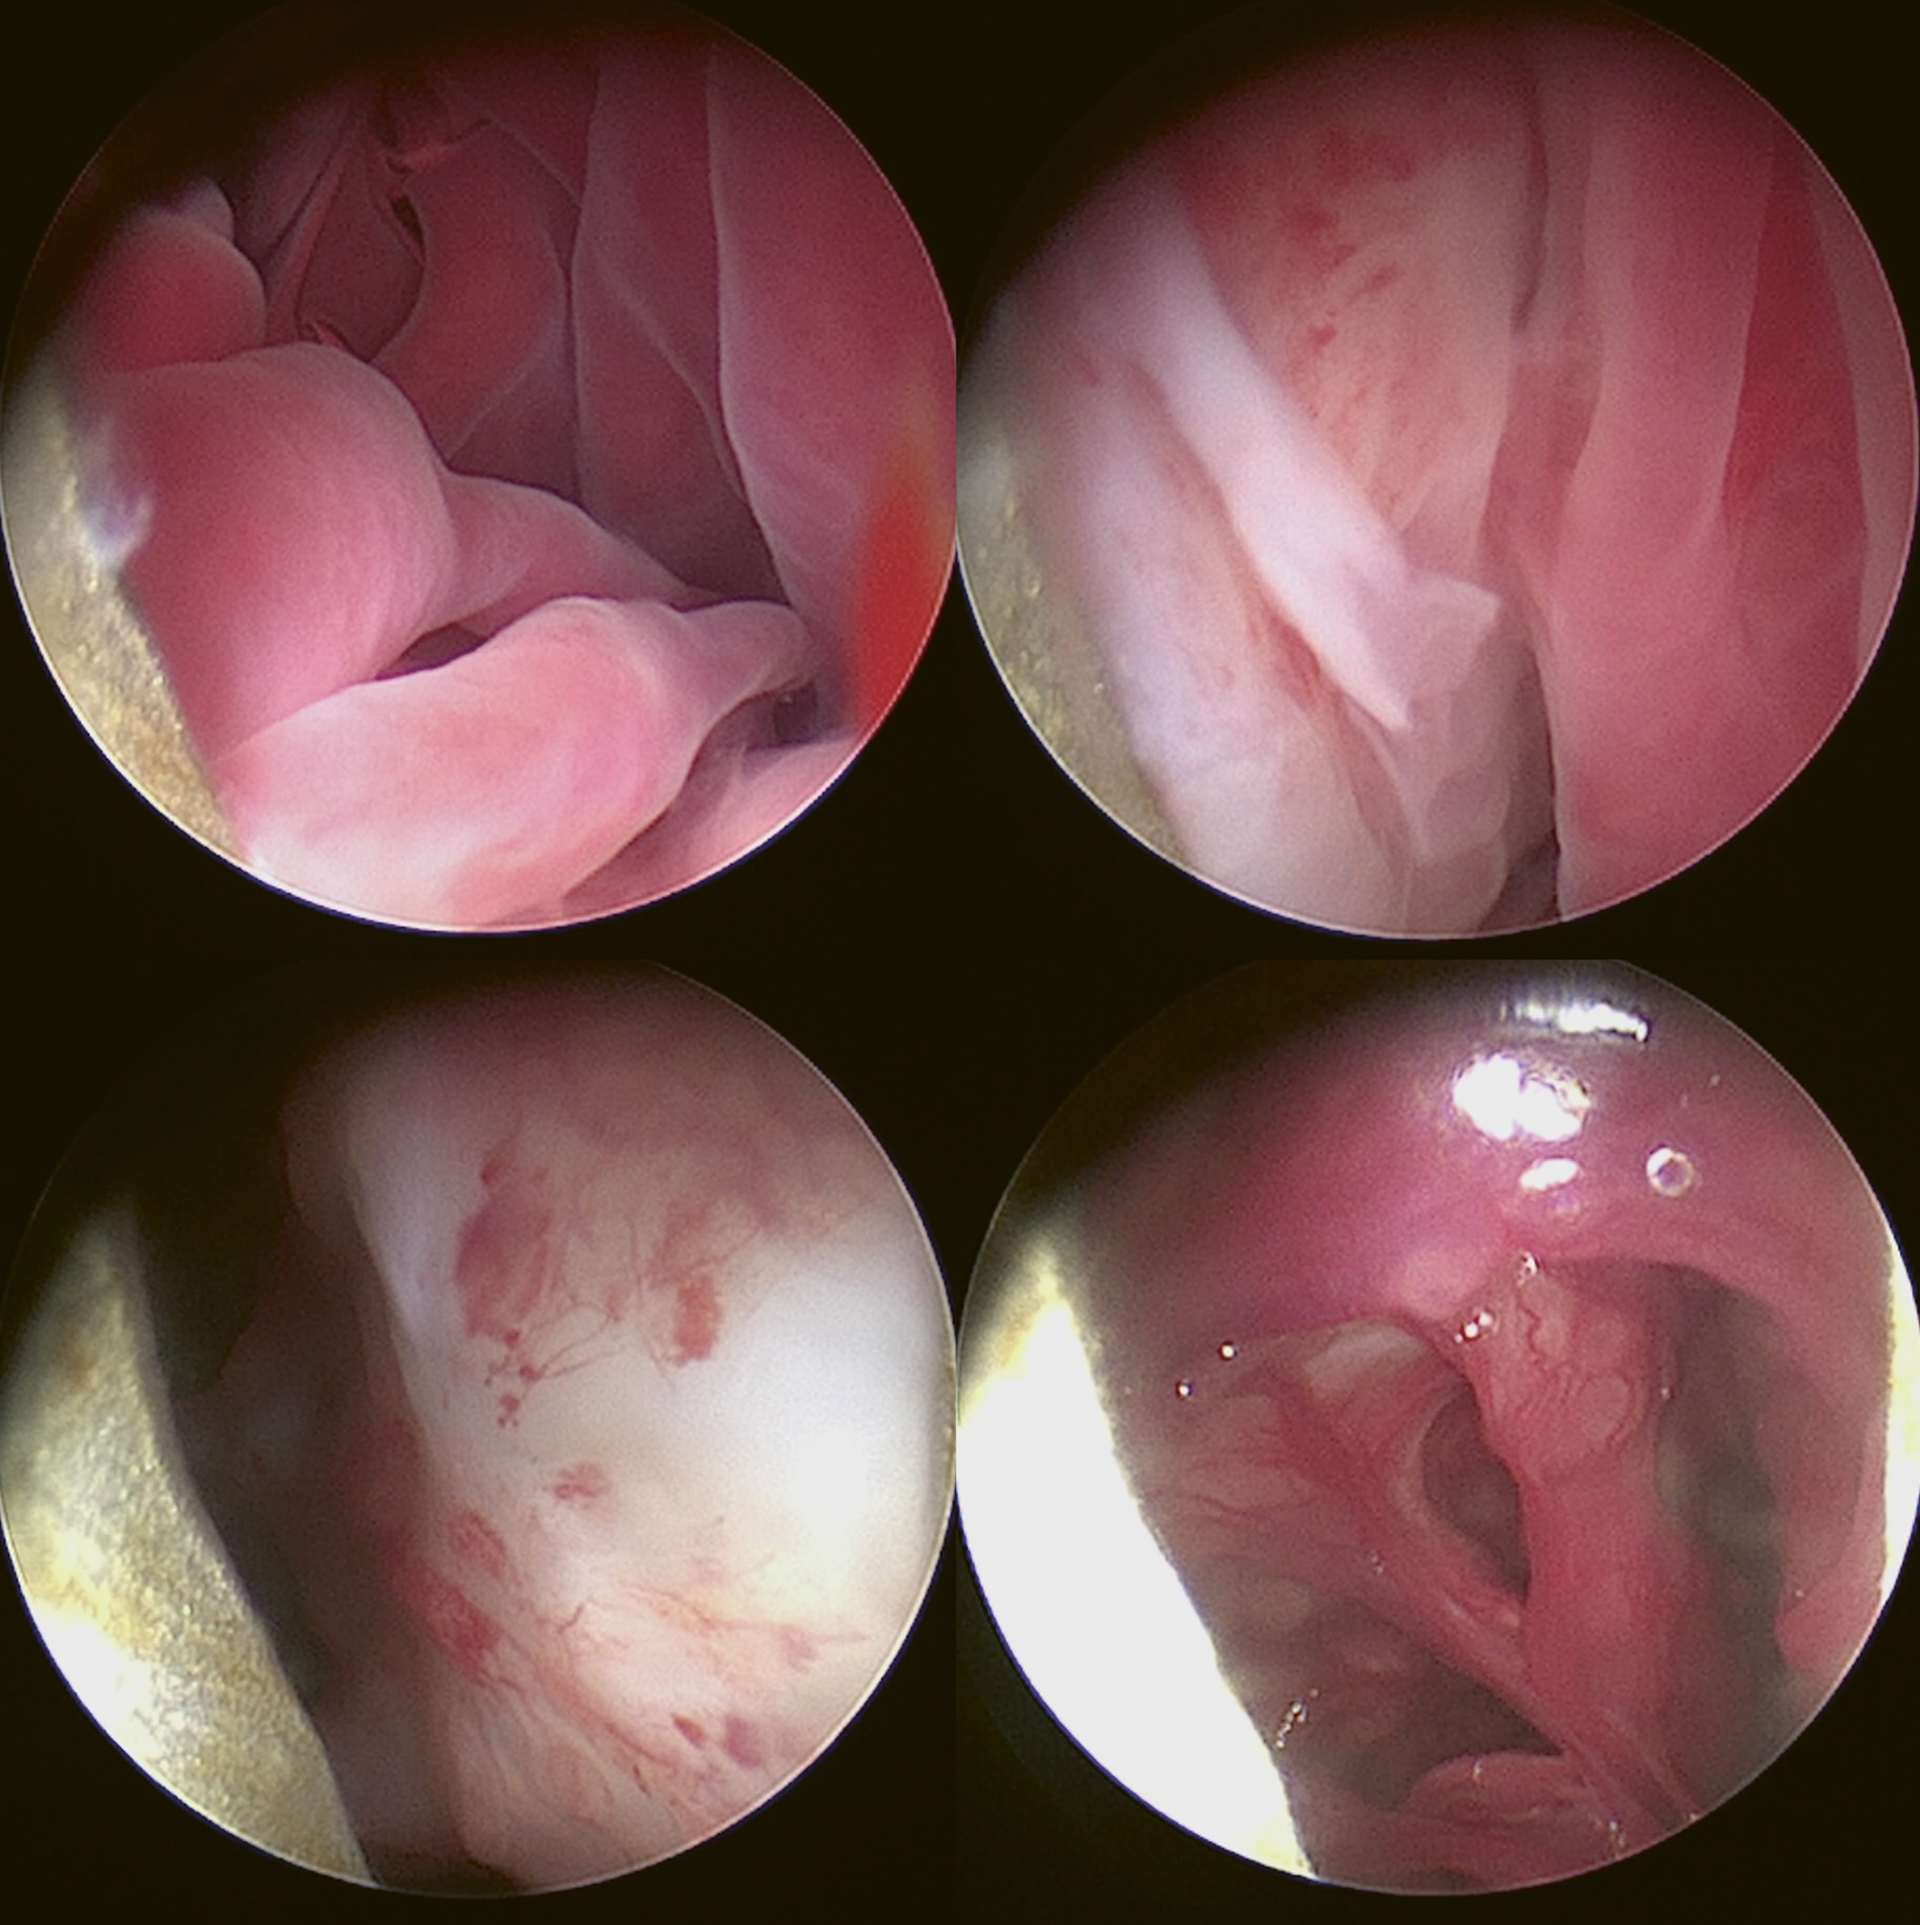

Figur 1. Rhinoskopiundersøkelse som viser nekrose, fragile slimhinner og gulhvite og grønnlige plakkformasjoner i høyre nesehule.

Larynx, pharynx og nasopharynx ble inspisert med et 3,5 mm fleksibelt Karl Storz engangs videoendoskop. Det kunne observeres mildt erytem over plica vocalis, rundt epiglottis og over et mindre område i nasopharynx. Svelget ble så pakket med kompresser før rhinoskopi ble utført. Rhinoskopiundersøkelsen ble utført med et 2,7 mm rigid Karl Storz Hopkins® Telescope 0° med hylse som hadde arbeidskanal og konstant vanntilførsel. Nesehulen ble inspisert systematisk fra ventrale nesegang, deretter over til midtre nesegang, og til slutt ble dorsale nesegang inspisert. Det ble observert gulhvite og grønnlige plakkformasjoner i midtre og ventrale nesegang bilateralt (Figur 1). Høyre halvdel av nesehulen var kraftig affisert, venstre halvdel var kun mildt affisert. Det ble i tillegg observert nekrose i høyre halvdel av nesehulen med fragilt vev som blødde og prellet vekk lett ved manipulering, samt små mengder pussdannelse. Slimhinnene var fragile og blødde lett ved manipulering bilateralt i nesehulen. Det ble plukket ut flere biter av plakket fra høyre halvdel av nesehulen ved hjelp av en gripetang. Vevsprøvene ble overført til EDTA-rør, flytende Amies mediumrør og i form av utstryk som ble sendt til analyse for mykologisk, bakteriologisk og cytologisk undersøkelse. Det ble laget et avtrykk av plakket fra nesehulen på et objektglass. Mikroskopisk undersøkelse av dette viste soppsporer (Figur 2).

Det ble anvendt samme anestesiprotokoll og medisineringsplan som sist, med unntak av paracetamol og fentanyl CRI. Ved rhinoskopiundersøkelsen var det ikke lenger synlige tegn til aspergillose. Slimhinnene var for det meste rosa av farge (Figur 8). I områdene som hadde vært mest affisert av aspergillose ved forrige undersøkelse var slimhinnen mer lyserosa eller hvit, og med rikelige mengder blodforsyning som indikerte sårheling. Det manglet som forventet brusk der nekrotisk vev og brusk var blitt fjernet ved forrige behandling. Det var i tillegg funn av en septumperforasjon. Nesehulen ble spylt med sterilt saltvann under rhinoskopiundersøkelsen. Deponering av klotrimazol i nesen ble gjentatt på samme måte som sist med okkludering av nesen, med unntak av trepanering som ikke ble vurdert som nødvendig (Figur 9). Dette for å bli kvitt potensielle rester av aspergillose i nesehulen som ikke lot seg visualisere via rhinoskopi. Hunden viste ingen nysing i etterkant av behandlingen.

Figur 8. Rhinoskopiundersøkelse uten tegn til nekroser eller plakkformasjoner etter vellykket behandling av aspergillose.